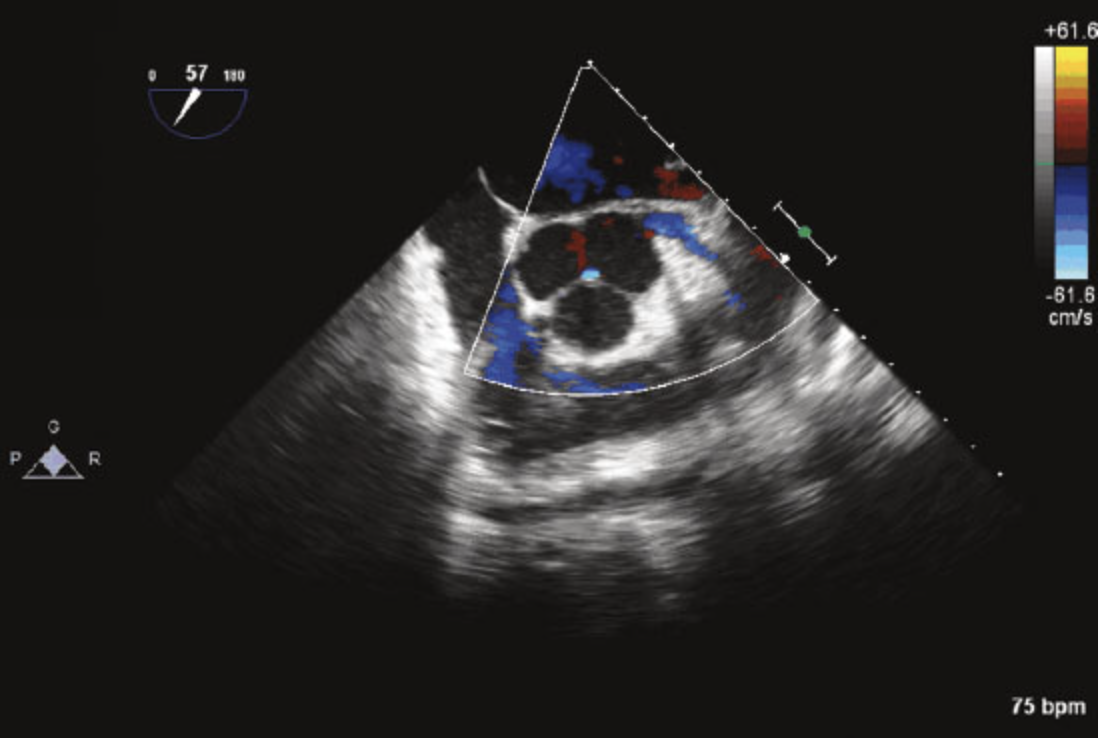

25

The abnormality of the aortic valve seen in Figure is consistent with:

This is an example of a unicuspid aortic valve. This is a relatively rare entity accounting for less than 5% of the adult population with aortic stenosis requiring surgery. Unicuspid valves can be unicommissural (most common) or acommissural.